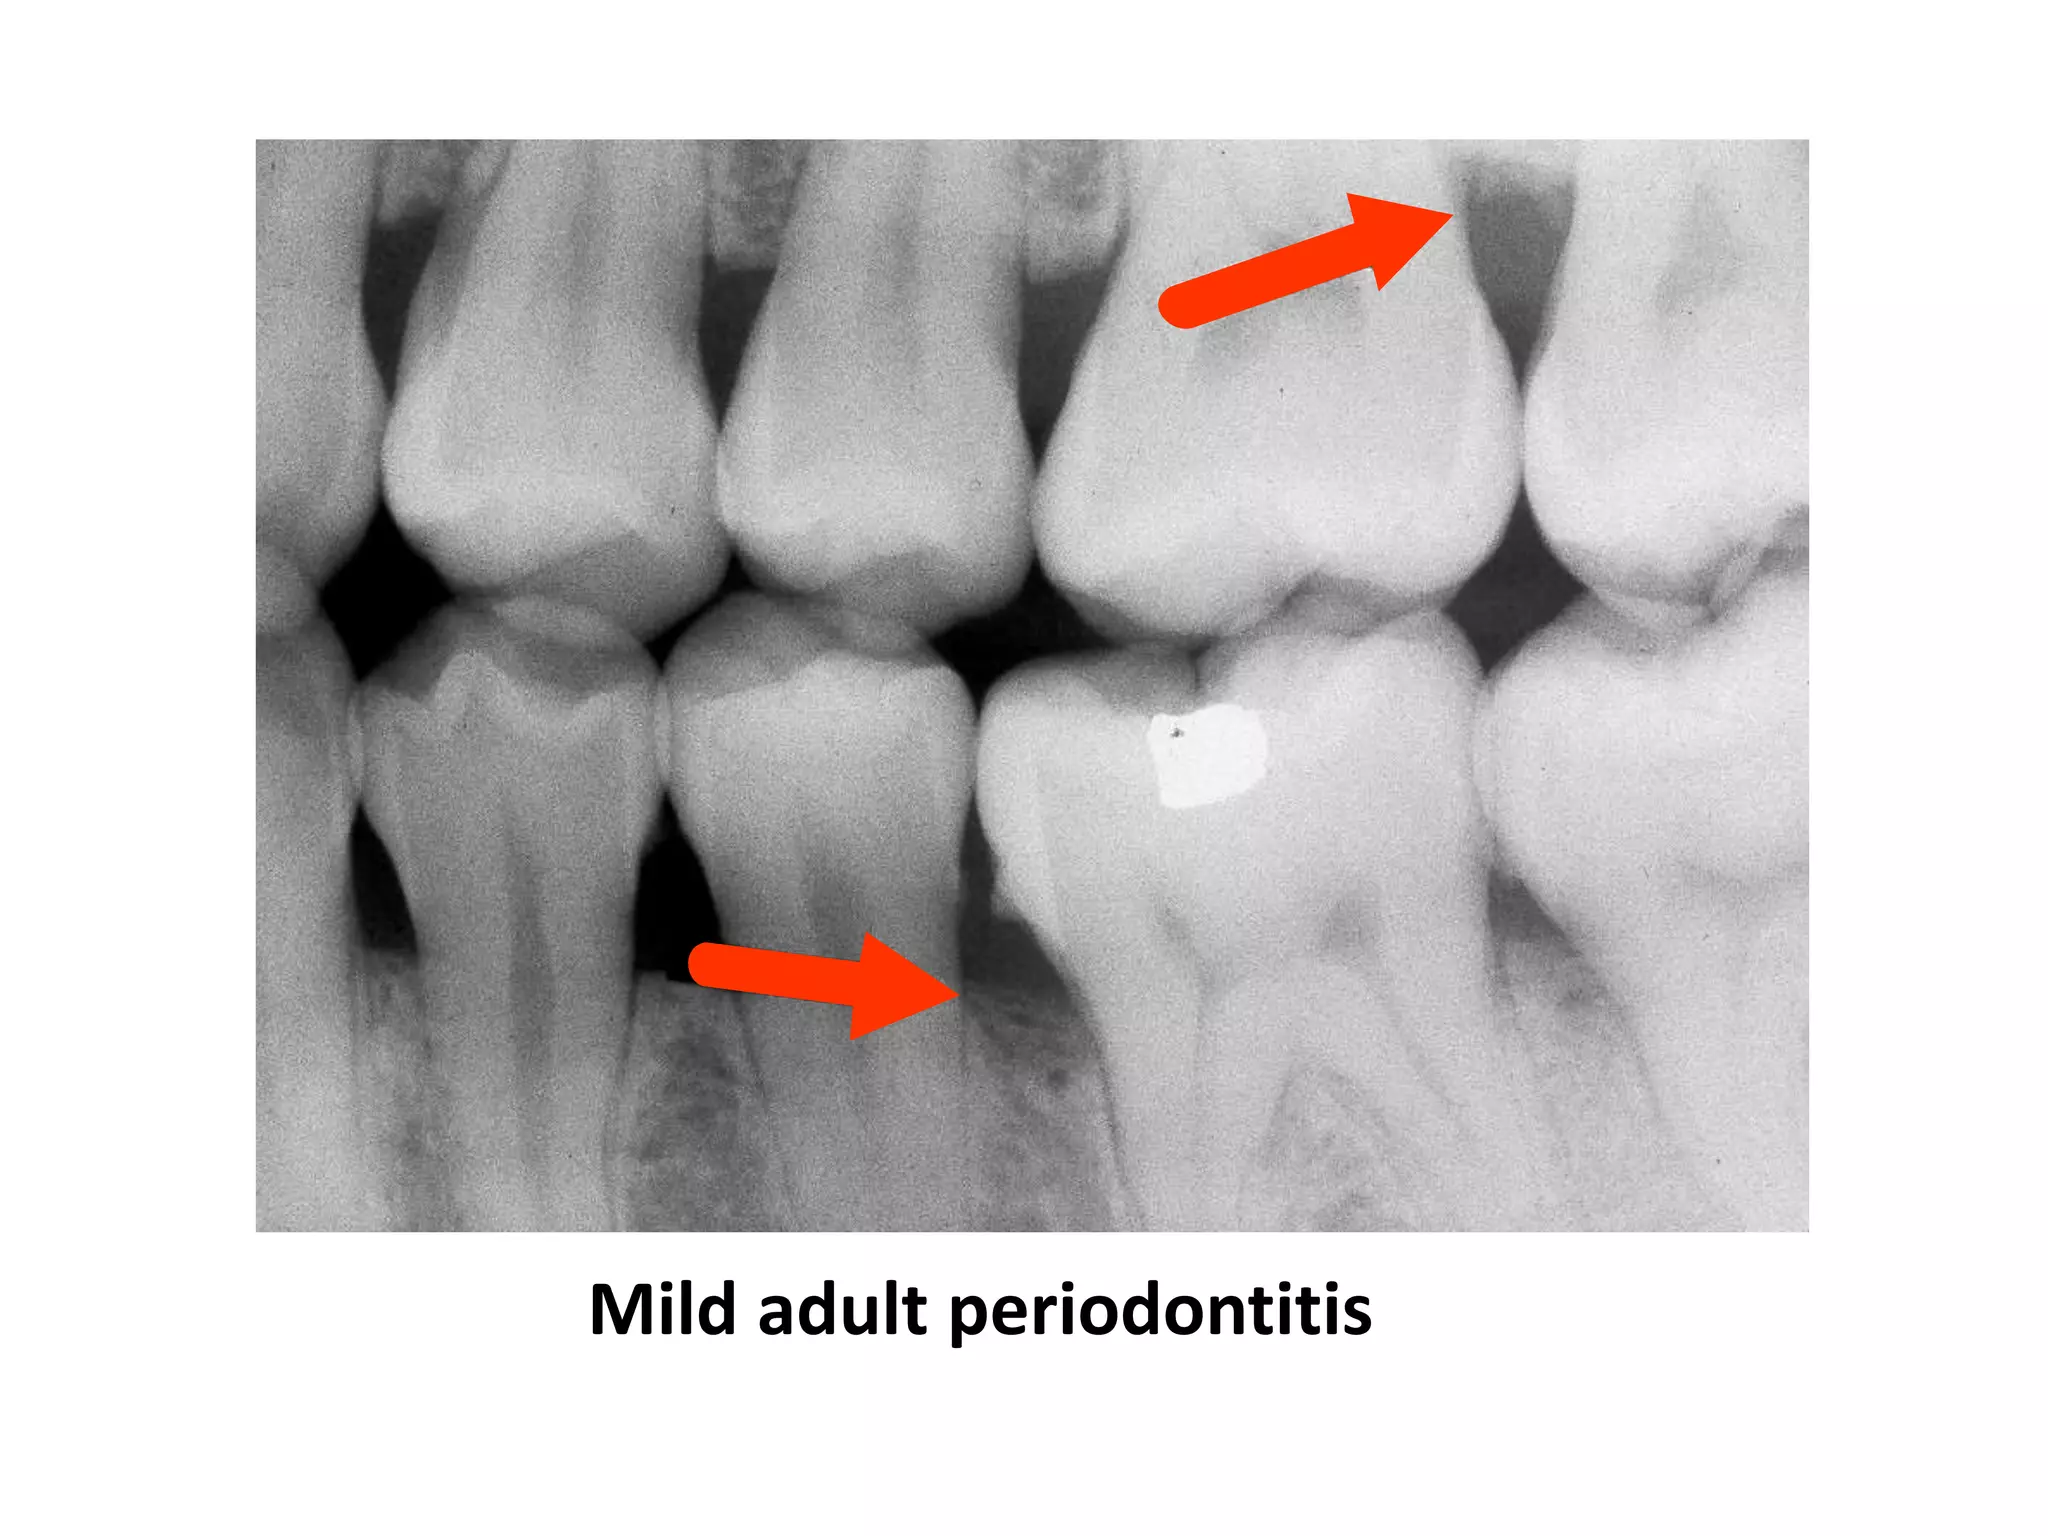

Mild Adult Periodontitis

Loss of cortical density

Rounding off of junction

between alveolar crest and

lamina dura

Blunting of crest anteriorly